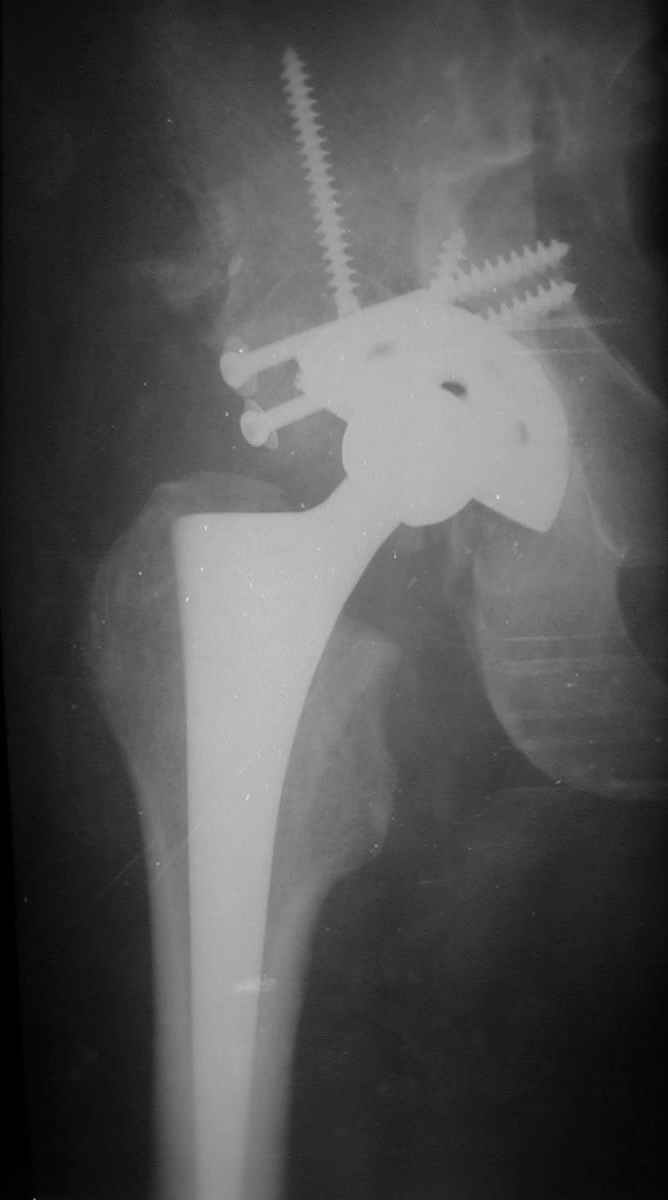

РАВ> Есть ли у Вас примеры установки протеза при обширных дефектах впадины?

РАВ> Какой был самый большой дефицит задней колонны, какой срок наблюдения,

РАВ> довольны ли Вы результатом?

Максимальные сроки наблюдения 5-6 лет. С появлением современных эндопротезов результаты сравнимы с первичным протезированием при обычном КА. Но, каждая операция нестандартная и требуется

тщательнейшее планирование каждого шага и необходимо иметь несколько запасных вариантов.

Схематично можно сказать так - если есть контакт с 60% и более ВВ, то этого достаточно для последующей биологической фиксации чашки. Опять же НО, мы стараемся "подрыться" фрезами так, что бы был приемлимый упор чашки, а фиксация аутотрансплантата головки была прочной без каких либо дефектов и зазоров.

Если у Вас есть дефект крыши, то никакая пластика не выдержит, лучше сразу ставить опорные кольца, все зависит от локализации костного дефекта.

В институте совместно с фирмой Зиммер достаточно регулярно (практически ежемесячно) проводятся 2-х недельные циклы по различным вопросам эндопротезирования. Если есть возможность и желание, мы готовы поделиться с Вами нашим опытом, тем более есть что показать и что обсудить - в настоящее время ежедневно выполняется от 6 до 10 эндопротезирований коленного и тазобедренного сустава. В качестве примеров хочу показать 2 наблюдения, через 1 год и 5 лет после операции

1 год